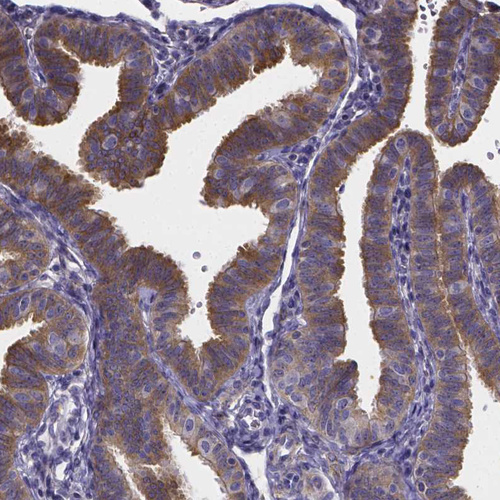

Immunohistochemical staining of human fallopian tube shows moderate cytoplasmic and membranous positivity in glandular cells.